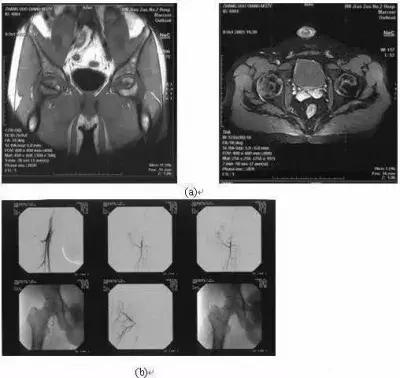

如果对Ⅰ、Ⅱ期股骨头尚未塌陷的患者进行介入治疗,从良好愿望推测其出发点是好的,但最终的结局仍是事与愿违,有的作者对有些股骨头坏死已达Ⅲ期(开始塌陷)或Ⅳ期(关节损坏),仍坚持用介入治疗,这种方法是不妥当,无效的(图2)。

图2:女性,32岁,皮质类固醇性股骨坏死(a)双侧股骨头已塌陷;(b)在此期仍做介入治疗

图3:男性,32岁,2003年10月8日(a)双髋关节MRI示骨坏死(Ⅱ期),2003年10月8日(

行介入治疗,2005年8月(c)X线示右股骨头仍进展至塌陷(Ⅲ期)